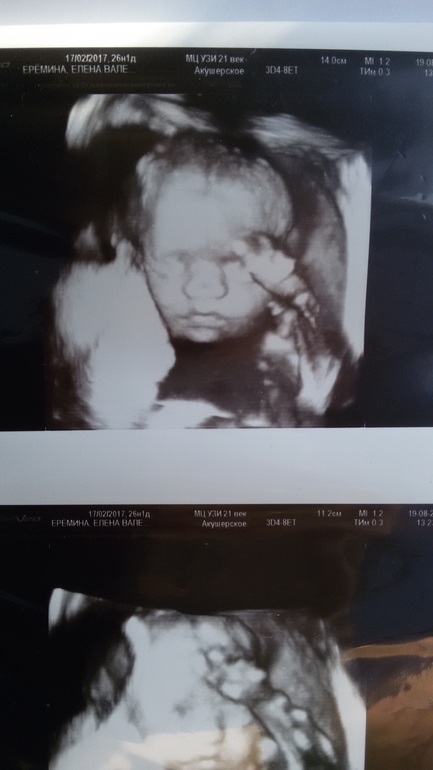

3. Фото .

Самое главное убедиться , что все хорошо с моим зайчиком, и тттт все хорошо,а то до 3 скрининга я не до терплю) второй скрининг делала в жк. и там в 20 нед.плаценту ставили 1 ст. зрелости,а нет зря переживала в 26.1 нед. на хорошем апарате 0-вая как и все бер.были,я выдохнула. Сегодня наш мальчик был в настроении, ни чего не скрывал и позировал)))😍наш любимый зайчик,все соответствует сроку 26 нед.1д. вес 880 гр., воды норма, плацента спереди,чсс 154.,я от встречи ввостоге  ну и наш человечек

ну и наш человечек